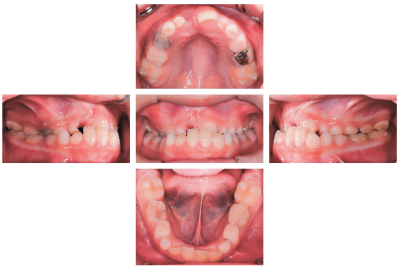

7歳の男児。前歯の咬み合わせが反対になっていることを主訴として来院した。乳歯列も同様であったという。診断の結果、矯正治療を開始することとした。初診時の顔面写真、口腔内写真及びエックス線画像を別に示す。セファロ分析の結果を図に示す。

第一期治療で行うのはどれか。3つ選べ。

a. 下顎骨の成長抑制

b. 上顎骨の前方牽引

c. 下顎前歯の舌側傾斜

d. 上顎歯列の側方拡大

e. 上顎右側中切歯の萌出誘導